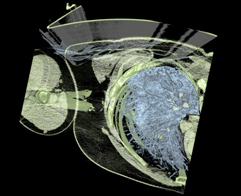

Medical

This is the medical-02 viewset from the SPECviewperf 13 graphics performance benchmark. It uses the Tuvok rendering core of the ImageVis3D (http://www.sci.utah.edu/software/imagevis3d.html) volume visualization program to render a 2D projection of a 3D volumetric grid. A typical 3D grid in this viewset is a group of 3D slices acquired by a scanner (such as CT or MRI).

Scan image from medical-02 viewset